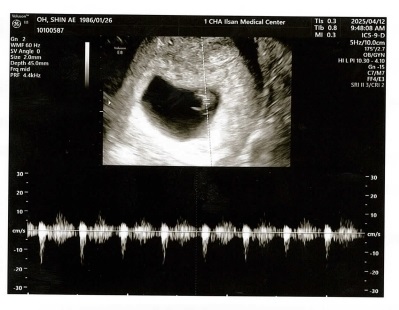

2025. 4. 12. 반디 1.3cm(7w 3d)

일산차병원 첫진료 지난 번 첫심장소리를 들었을 때 반디가 0.5cm 정도 된다고 들었었는데 1주일만에 과연 ...